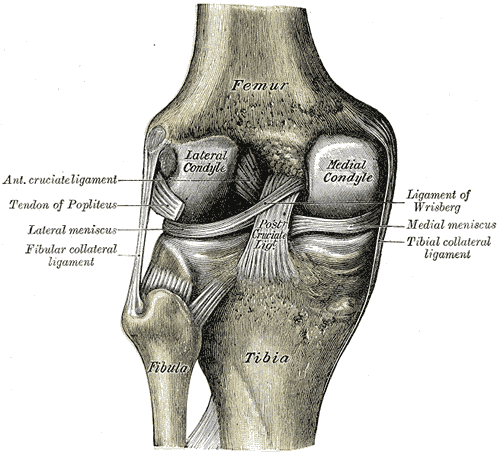

visão posterior da articualçaõ do joelho - fonte:Wikipedia